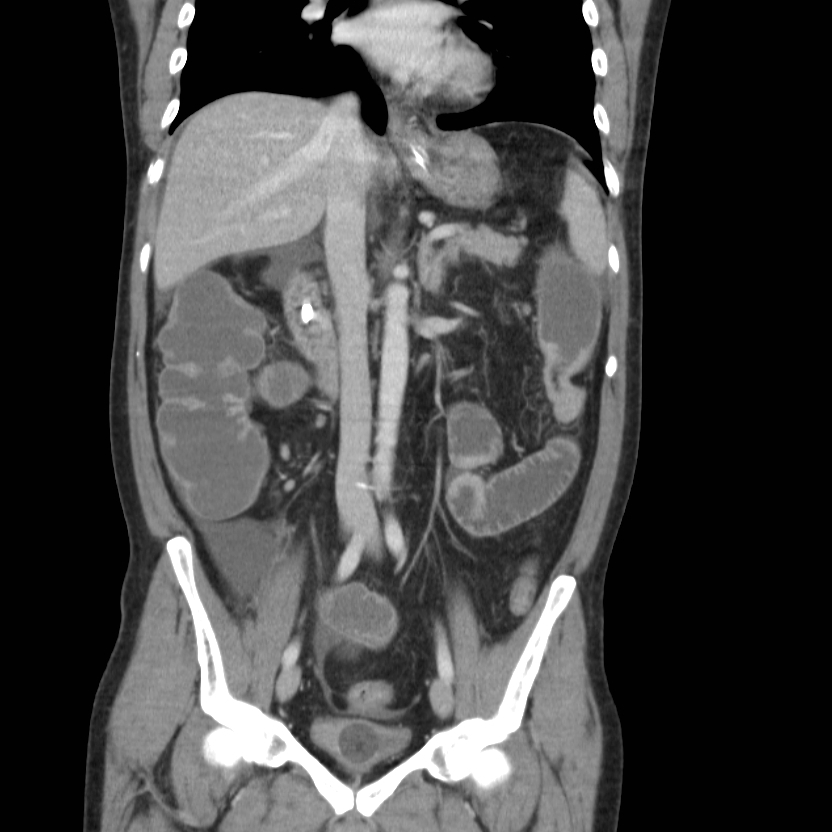

Complications of Chronic Pancreatitis

Generalised atrophy of body and tail of the pancreas. Diffuse parenchymal calcification with main pancreatic duct dilated throughout its course with a beaded appearance reaching up to 10mm in diameter. Multiple intraductal calculi are present, the largest measuring 10 mm in the pancreatic head. This stone is obstructing the main pancreatic duct resulting in ductal dilatation. No hypoenhancing pancreatic parenchymal lesions. No peripancreatic fat stranding or localised collections. No radio-opaque stones in the gallbladder, cystic duct, or common bile duct. No intrahepatic biliary duct dilatation.

Case Discussion

When presenting with an episode of abdominal pain, this patient underwent an ultrasound of the abdomen which revealed features of chronic calcific pancreatitis. However, due to the suboptimal acoustic window, a CT scan was recommended to rule out any pancreatic inflammation or neoplasm. The chronic inflammatory changes result in reduction in volume of pancreatic parenchyma with only a ghost of the gland remaining in the latter stages. These patients are more prone for neoplasms and have to be watched closely.